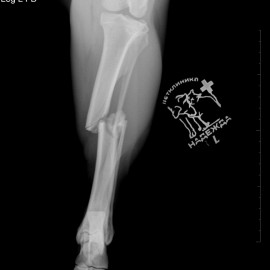

Наш пациент после автотравмы. Был проведен остеосинтез левой голени, в ходе которого была установлена динамическая титановая пластина с винтами. Так же были наложены серкляжные швы из титановой проволоки. Состояние пациента хорошее. Лапой пользуется активно.

Снимок 1-2 до операции.